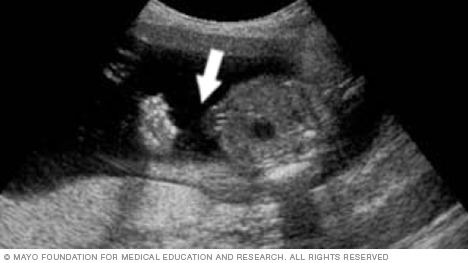

The arrow in the image below points to the site where the umbilical cord is attached to the fetus's belly, also called the abdomen. By looking at this area, the health care team can check for several conditions. They include a condition called omphalocele. It happens when contents of the abdomen come out through an opening at the bellybutton. Another condition is gastroschisis. It involves a break or split in the tissue that forms the abdominal wall.